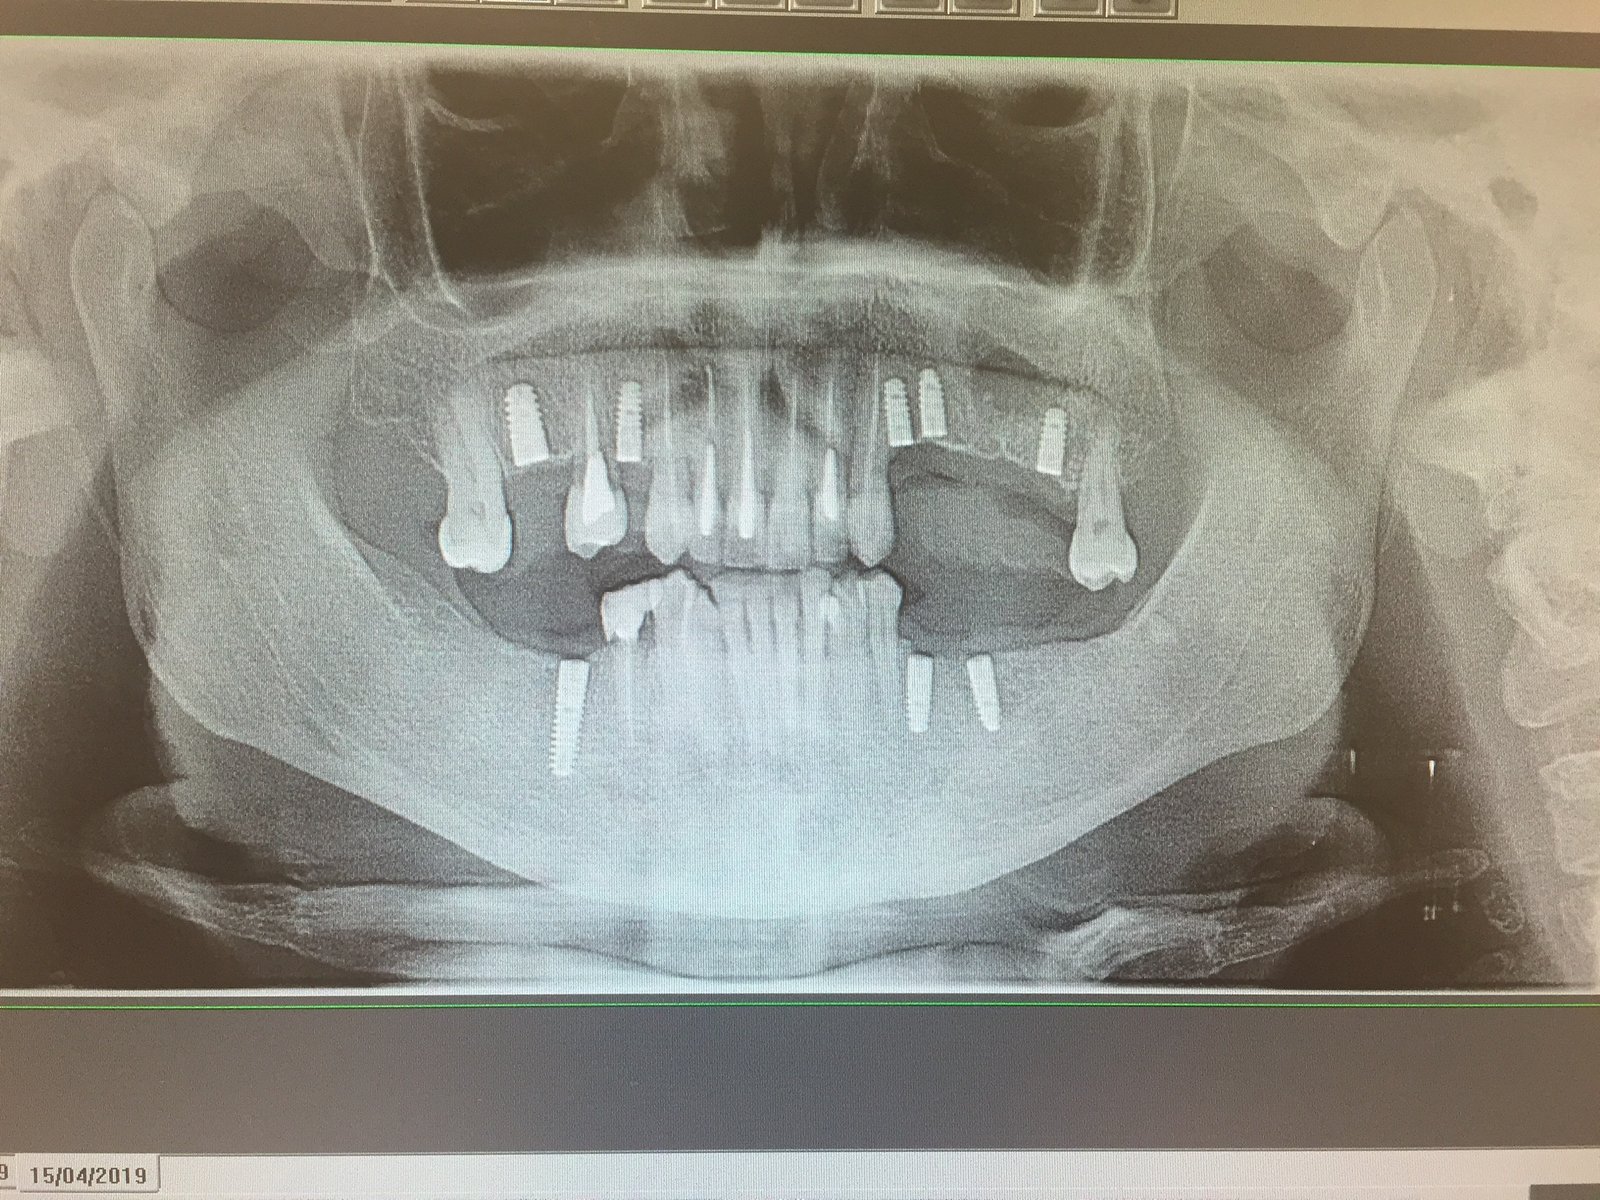

Buenos días, adjunto el caso de una paciente que acude a la clínica con 4 implantes colocados hace años y con una barra y sobredentadura. La sobredentadura solo apoya en [...]